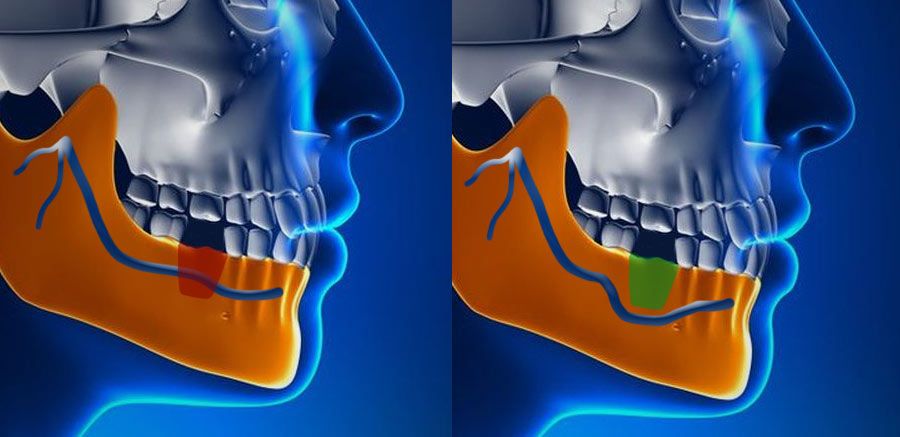

Nerve Repositioning

The inferior alveolar nerve, which gives feeling to the lower lip and chin, may need to be moved in order to make room for the placement of dental implants in the lower jaw. A nerve repositioning procedure is limited to the lower jaw and may be indicated when teeth are missing in the area of the two back molars and/or second premolars. This procedure is considered a very aggressive approach since there is almost always some postoperative numbness of the lower lip and jaw area, which typically dissipates very slowly, but may be permanent. Usually other, less aggressive options are considered first (placement of blade implants, etc).